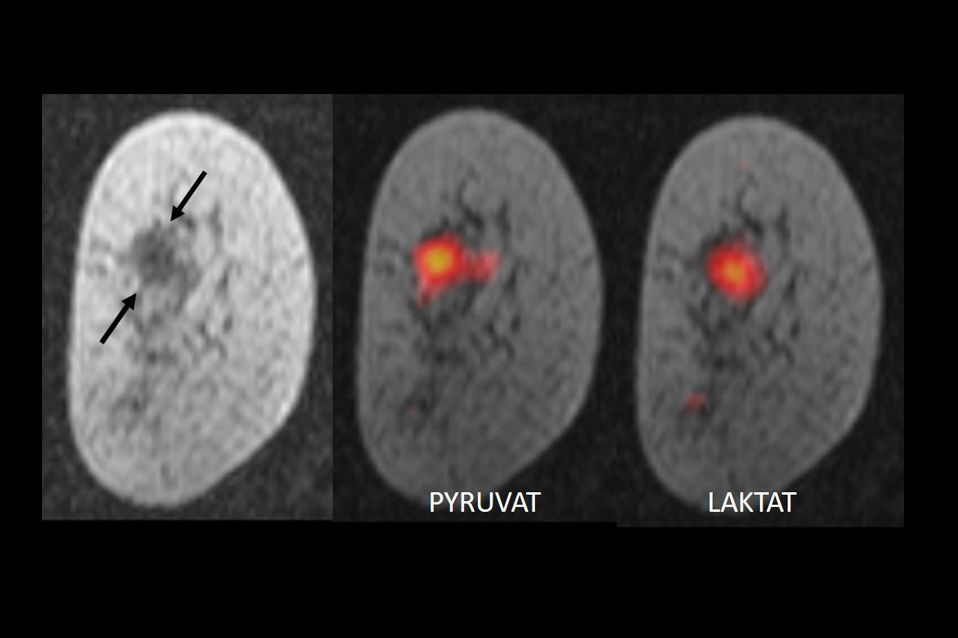

The group at the University of Cambridge labelled pyruvate, a substance that occurs naturally in the body, with the non-radioactive carbon isotope C-13 and then magnetised it. To do this the labelled pyruvate is cooled to -272°C and exposed to very strong magnetic fields and to microwave radiation – this process is also known as "hyperpolarisation". Once the substance has been thawed and dissolved, it is injected into patients. Due to the magnetisation, the signal strength of the C-13 pyruvate in MRI is increased 10,000-fold so that MR images of the tumour metabolism can be produced within seconds. Normally, the body's cells convert pyruvate into lactate. Due to their altered metabolism, tumour cells convert pyruvate to lactate much more rapidly – the speed of the process varying between different tumours and also within the tumour itself. Using MRI, it is not only possible to observe the quantity of the specially treated pyruvate in different tissues but also to observe the conversion process in real time. The researchers demonstrated that this provides information about the nature of the tumour and how aggressive it is.

"This is one of the most detailed images of the metabolism of breast cancer that we have ever had. It is as if we can see the tumour breathing," explains Kevin Brindle from the Cancer Research UK Cambridge Institute, one of the originators of the technique, in a press release.